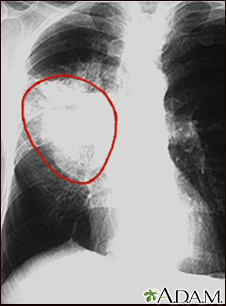

Lung cancer - frontal chest x-rayBackLung cancer - frontal chest x-rayA chest x-ray in a patient with central cancer of the right lung. Notice the white mass in the middle portion of the right lung (seen on the left side of the picture). E-mail FormEmail ResultsName:Email address:Recipients Name:Recipients address:Message: